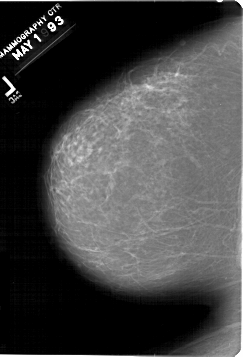

A_1421_1.LEFT_CC

LEFT_CC LINES 6766 PIXELS_PER_LINE 4606 BITS_PER_PIXEL 12 RESOLUTION 43.5 NON_OVERLAY